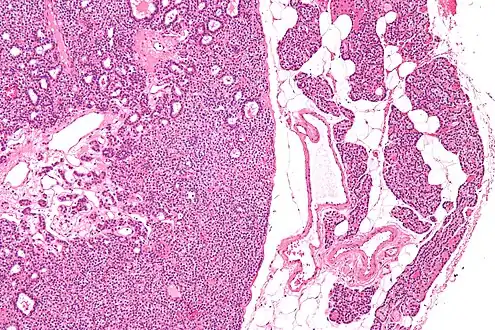

| Micrograph of a parathyroid adenoma (left) and normal parathyroid gland (right). H&E stain. | |